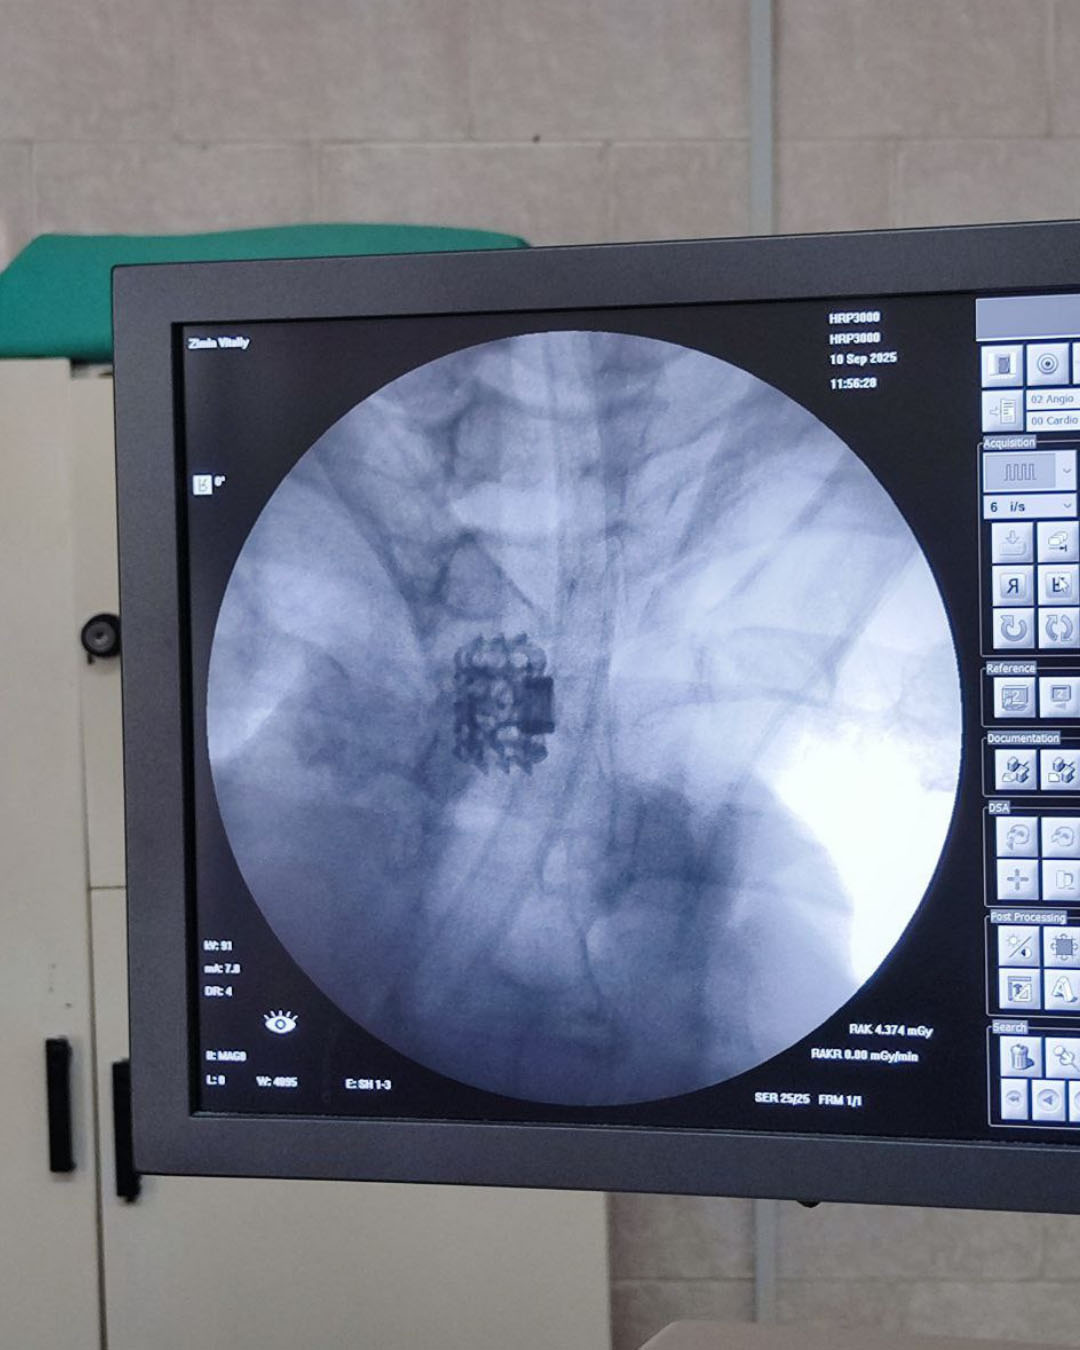

Малоинвазивные операции позволяют сократить время восстановления пациента, минимизировать риск осложнений и снизить уровень боли после вмешательства. Операция продолжалась всего 2,5 часа и проводилась с использованием торакоскопического метода. В процессе операции был использован индивидуально разработанный комплекс для стабилизации позвоночника, который включает в себя бокскаттер и имплант со сквозной пористостью стенки.

Изготовление компонентов системы стабилизации осуществлялось на сертифицированном оборудовании с использованием 3D-печати. Апробация данной системы проводилась на протяжении двух лет, в ходе которых открытое оперативное лечение получили 65 пациентов.